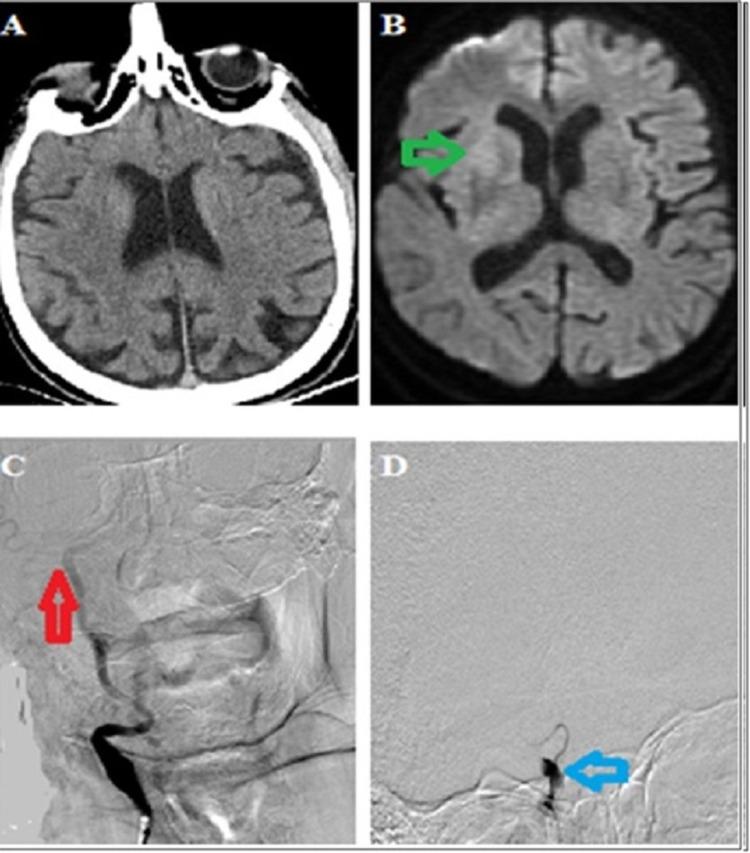

COVID-19 disease causes various neurological disorders. Of these, stroke is the most devastating and difficult to manage in epidemic conditions. An increase in the rate of acute ischemic stroke in hospitalized coronavirus patients and stroke with large vessel occlusion due to COVID-19 disease have been reported in recent publications. The management of these patients is difficult and becomes even more challenging in epidemic conditions. A 71-year-old man suddenly developed left-sided weakness while he was hospitalized for COVID-19 disease. Cerebral computed tomographic angiography showed a terminus of the right internal carotid artery. The occluded vessel was completely recanalized by endovascular therapy. Left-sided hemiparesis resolved completely. As a result of this study, cryptogenic stroke was considered in the etiology of stroke. In this report, we present a case of stroke with COVID-19, who developed large vessel occlusion accompanied by splenic infarction while hospitalized due to COVID-19 disease and was successfully treated with endovascular thrombectomy under epidemic conditions.

新型冠状病毒肺炎(COVID-19)可引发多种神经系统疾病。其中,中风最为严重,在疫情期间也最难处理。近期发表的文献报道了住院的冠状病毒患者急性缺血性中风发生率增加以及因COVID-19疾病导致的大血管闭塞性中风。这些患者的治疗难度很大,在疫情期间更是极具挑战性。一名71岁男性在因COVID-19疾病住院期间突然出现左侧肢体无力。脑部计算机断层血管造影显示右侧颈内动脉末端闭塞。通过血管内治疗,闭塞血管完全再通。左侧偏瘫完全缓解。基于本研究结果,中风病因考虑为隐源性中风。在本报告中,我们介绍了一例因COVID-19疾病住院期间发生大血管闭塞并伴有脾梗死的COVID-19相关性中风病例,该病例在疫情条件下成功接受了血管内血栓切除术治疗。